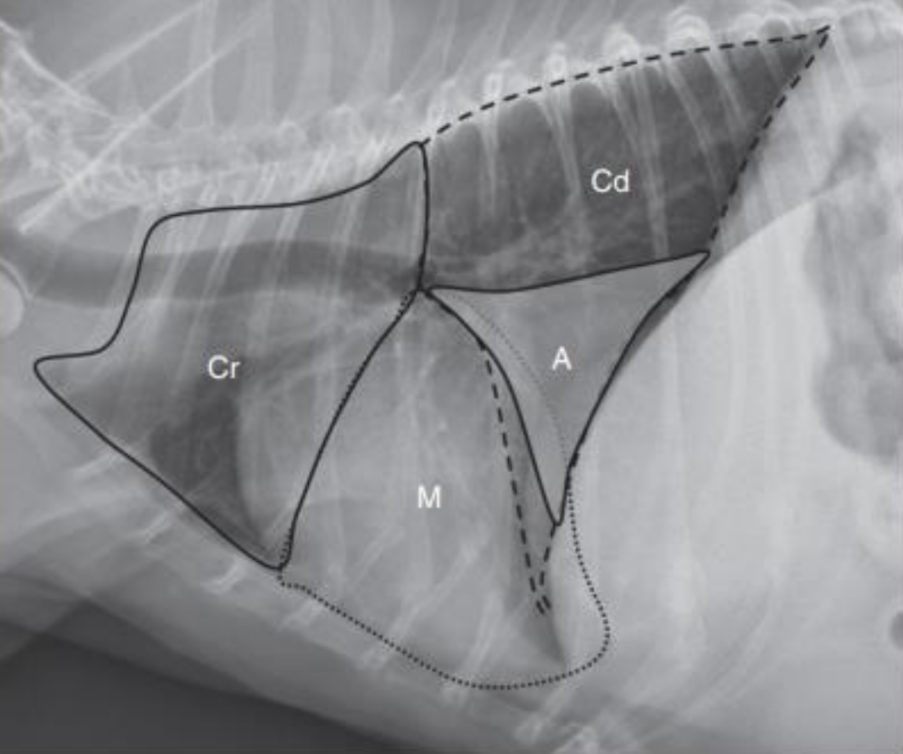

1. Normal Anatomy